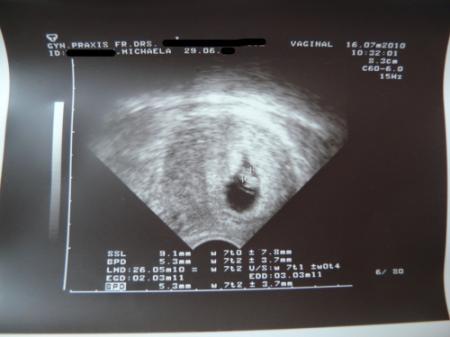

ich komm gerade vom Ultraschall

Und wir haben unser Baby gesehen, sooo schön :-))

Unser Baby hat einen Kopf, einen Körper (man kann sogar schon erkennen, was mal Arme und Beine werden sollen) - und das allerwichtigste: unser Baby hat ein schlagendes Herz

Vom Kopf bis zum Po ist es 9,1 mm groß, also fast schon ein ganzer cm :-))

Laut Ultraschall ist der Termin am 03.03.11, das ist ein Tag später als errechnet, also alles zeitgerecht entwickelt :-))